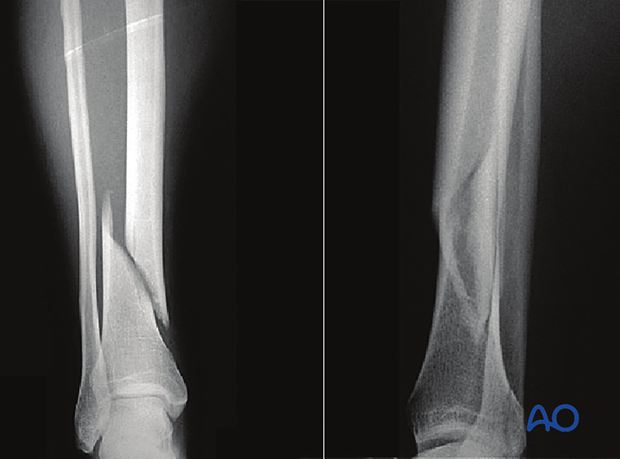

This is a simple spiral fracture of the tibial shaft with a proximal fibular neck fracture.

Lateral image of the same fracture.